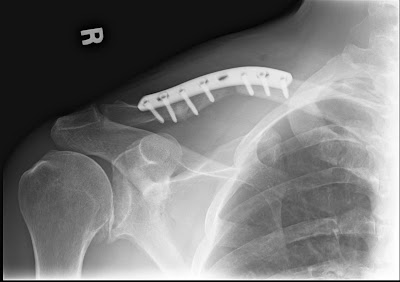

As you can see, the pieces of bone definitely line up better than before. Dr. Loucks says it won't ever be perfectly symmetrical, but the big bump on my right shoulder (caused by the broken bone sticking up) is gone. More importantly, it no longer moves around! What I had before surgery was a "